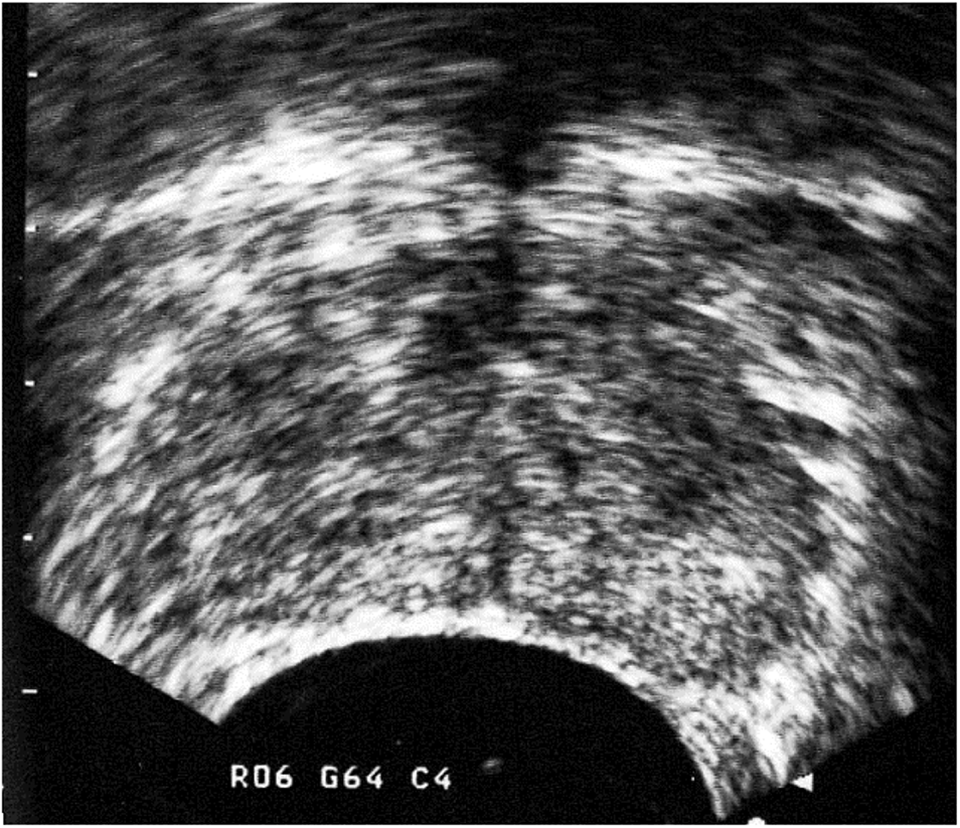

Figure 4: Tomogram of the prostate with very early prostatic cancer, taken by our commercial chair with electronic scanner. A hypoechoic legion was observed in the central part of the left (right on the picture) lobe

Later, following the advancements at Wake Forest, Dr. Rifkin, one of the U.S. leaders in TRUS, began using a linear scanner from the Japanese company “Toshiba” and noted that prostate cancer showed a “hyper-echoic pattern” on the ultrasonogram. In contrast, Dr. Fred Lee, another key figure in TRUS, used a “B&K” machine and emphasized that prostate cancer appeared as a “hypo-echoic pattern.” His slogan, “Cancer is black,” became widely recognized during that period. Modern ultrasound machines show that early, small cancerous lesions in the prostate always appear hypoechoic (Figure 4). Dr. Rifkin may have been observing only more advanced cases, which tend to have stronger echo reflections.